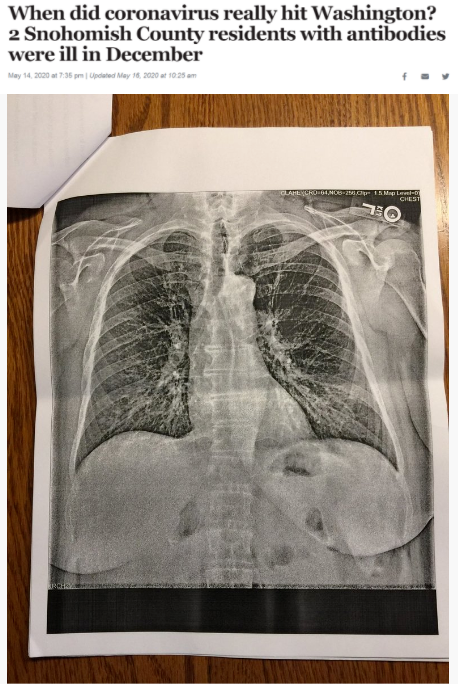

據(jù)《西雅圖時報》去年5月14日報道,華盛頓州斯諾霍米什縣的兩位居民在2019年12月出現(xiàn)類似新冠肺炎的癥狀,之后對他們的新冠病毒抗體檢測呈陽性反應(yīng)。這一結(jié)果表明,新冠病毒可能比想象中更早在當?shù)爻霈F(xiàn)。

△《西雅圖時報》報道截圖(題圖中的X光片顯示其中一位斯諾霍米什縣居民的肺部“過度充氣”并出現(xiàn)“線性混濁”。醫(yī)生認為,這可能是疊加上呼吸道肺部感染的表現(xiàn)。)